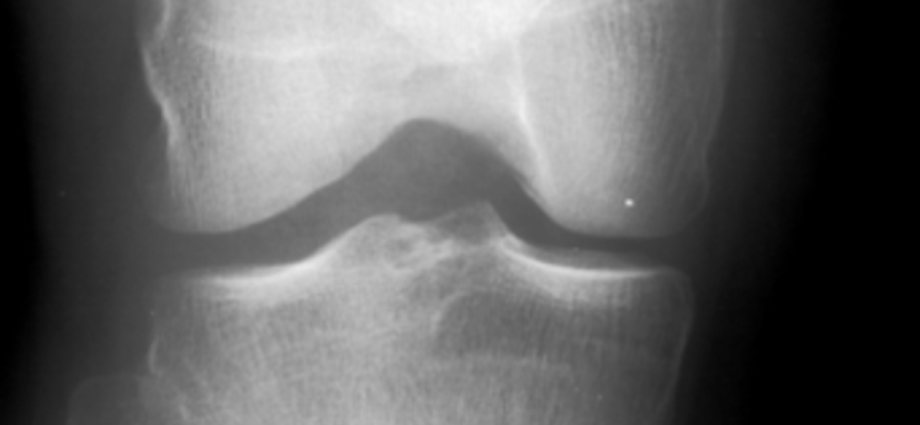

Osteoarthritis, a degenerative joint disease, affects nearly a quarter of adults and is a leading cause of disability worldwide.

It occurs when the cartilage cushioning the ends of bones wears down, leading to pain, stiffness, and reduced mobility.

Researchers focused on patients with mild-to-moderate osteoarthritis in the medial compartment of the knee, the inner side of the joint, which typically bears more weight than the outer, lateral compartment.